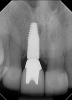

Fig 3. In a separate case, radiograph of a decayed endodontically treated tooth is shown. The decision was made to extract it before further damage to adjacent teeth and/or loss of bone could occur.

Figure 3

Fig 4. Radiograph of the implant to replace the tooth in Fig 3 (implant placed by David Levine, DDS).

Figure 4

Fig 5. Successful final clinical result of the implant restoration and adjacent teeth.